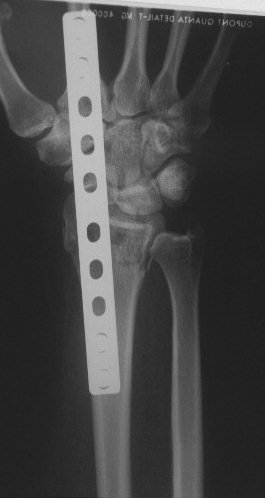

Clinical Example: Distraction plate fixation of distal radius fracture

A tricky case, for the patient previously had a large skin graft over the dorsal metacarpus / wrist / forearm. Incisions are marked here just before the plate was removed.